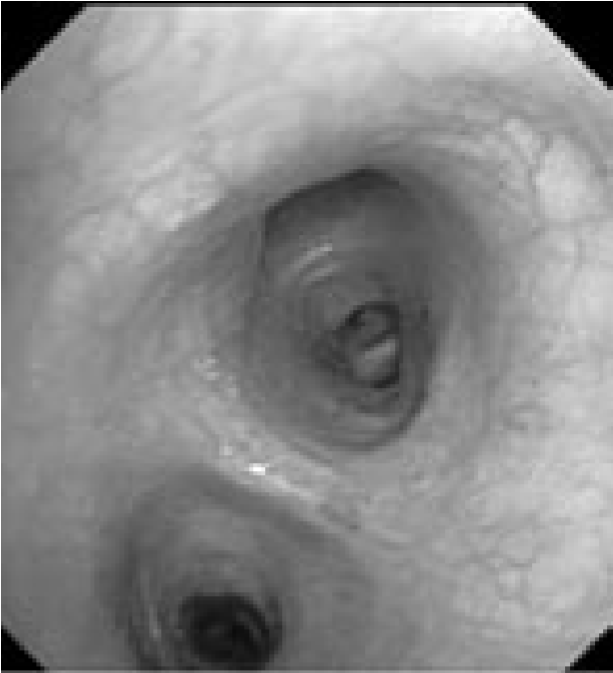

В связи с сочетанным характером патологии (поражение как легочной ткани, так и средостения) было запланировано проведение комбинированного двухэтапного эндоскопического исследования. На первом этапе предполагалось выполнить видеобронхоскопию в стандартном разрешении с детальным осмотром верхнезонального бронха левого легкого, бронхоальвеолярный лаваж (БАЛ), при наличии технической возможности – браш-биопсию и щипцовую трансбронхиальную биопсию легкого. На втором этапе планировалось провести эндоскопическую ультрасонографию средостения эхобронхоскопом (ЭУС-б) с визуализацией бифуркационного лимфоузла с последующей тонкоигольной пункцией. Все исследования планировалось осуществить в условиях местной анестезии. 23.08.2017 г. пациенту выполнена видеобронхоскопия бронхоскопом Olympus BF 1Т150 (Olympus Corp., Japan). Интубация проведена через правый носовой ход. По результатам исследования гортань без особенностей. Трахея свободна, отделяемого нет. Бифуркация не расширена, карина острая, подвижная, устья бронхов 1–5-го порядка справа открыты, не деформированы, в просвете сегментарных бронхов единичные комочки слизистой мокроты. Слизистая видимых бронхов справа несколько отечна, гиперемирована. Слева: при осмотре бронхов верхней доли определяется перибронхиальный стеноз устья LВ1-2 до 3 степени, признаков пролиферативного поражения слизистой в указанной зоне нет. При акваскопии – устье стенозированного бронха открывается, признаков специфического поражения слизистой не выявлено. Слизистая бронхов слева умеренно гиперемирована, отечна (рис. 2).2

Рис. 2. Видеобронхоскопия пациента А., эндофото:

а – шпора верхнедолевого бронха левого легкого, визуализируется просвет нижнедолевого бронха (на 6 часов), на 12 часов – устья язычковых бронхов и верхнезонального бронха левого легкого; б – устье верхнезонального бронха левого легкого (LB1-2 и LB3), четко визуализируется продольный характер складчатости слизистой; в – детальный осмотр ветвей верхнезонального бронха: визуализируется перибронхиальное сужение устья LB1-2 до практически полного исчезновения просвета, дистальные ветви данного бронха осмотру недоступны, устье LB3 без особенностей, отмечается точечная пигментация слизистой над устьем LB1-2; г – осмотр устья бронха LB1-2 с помощью акваскопии (введение лаважного раствора в устье бронха под давлением) – признаков опухолевого либо специфического (туберкулезного) поражения слизистой не выявлено; д – осмотр устья бронха LB1-2 после выполнения акваскопии и забора БАЛ – скудное поступление пенистого отделяемого (по сравнению с активным дренажом из устья LB3 – на 4 часа); е – попытка выполнения щипцовой трансбронхиальной биопсии через устье LB1-2 (визуализируются бранши биопсийных щипцов – на 4 часа).